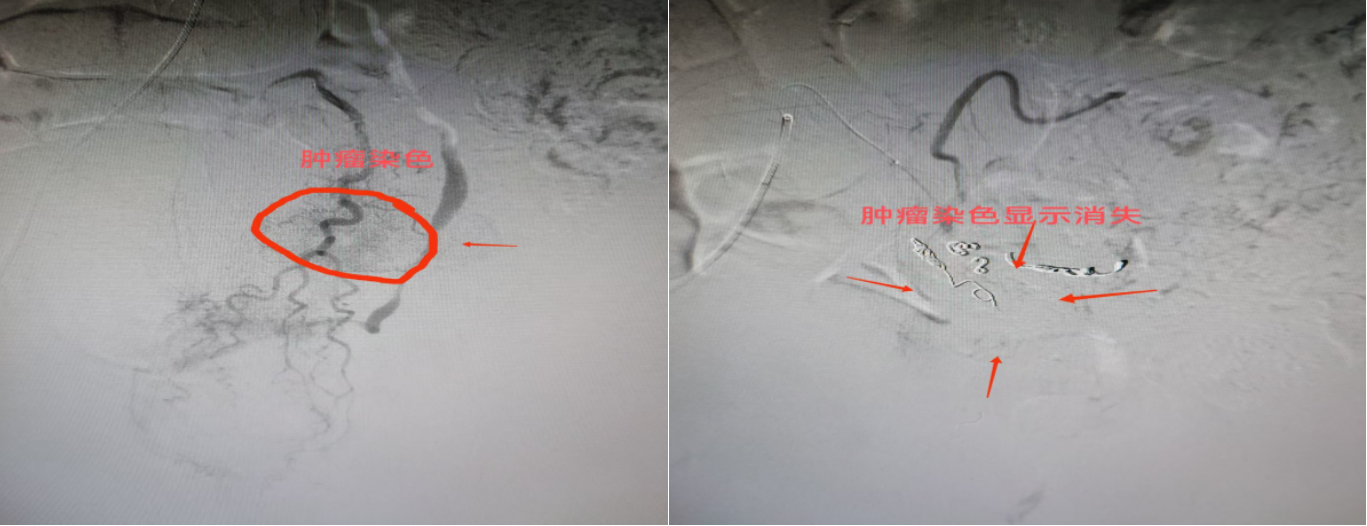

手术面临巨大挑战:患者超高龄、血管严重迂曲、肿瘤供血动脉杂乱无章、超选困难,且心肺功能欠佳、配合度低。在张文彬主任的带领下,团队迎难而上,紧急为患者实施数字减影血管造影(DSA)检查,精准定位到肿瘤附近的出血责任动脉。术中,医疗团队通过股动脉穿刺建立介入通道,运用精湛的微导管技术,将栓塞材料精准送达出血血管。凭借丰富的临床经验,团队耗时2小时成功封堵4处出血点,术后造影显示肿瘤相关血管网被完全封堵,出血停止。